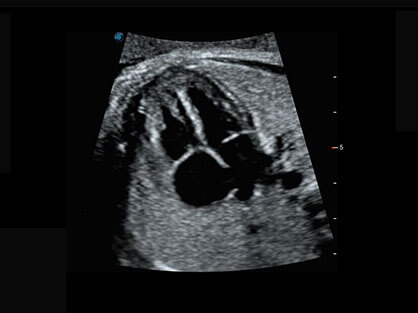

作为P系列家族成员之一,P40 Plus采用九州酷游高端超声系统平台——极光,并以时尚秀丽、小巧灵动的外观设计绽放出灵动之韵、科技之美。高端平台的使用保证了P40 Plus优质的基础图像;完备的高级功能可满足您全身应用的基本需求;丰富的探头配置、多样的高级4D成像及分析软件为您日益增多的妇产应用需求提供丰富的诊疗方案。

结合九州酷游超宽频带探头技术优势,能够更好地获得高分辨力与高穿透力的平衡,保证图像质量,为临床诊断保驾护航。

微米成像技术提升了对组织斑点噪声信号的抑制能力,并进一步强化边界信息,从而获得清晰图像。